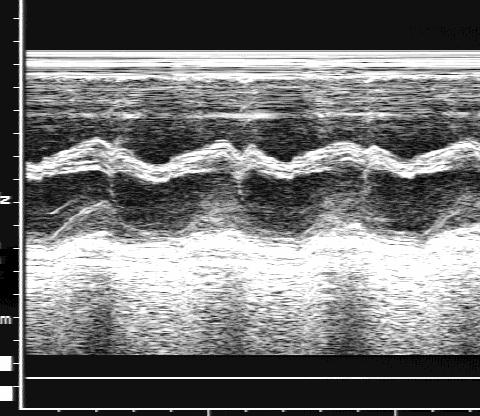

Перимембранозный дефект межжелудочковой перегородки.

Рис.82.

Перимембранозный

дефект

межжелудочковой

перегородки:

в одномерном

исследовании виден

перерыв эхосигнала

от перегородки

(нарушение переднего

аорто-септального

контакта).

Одномерная ЭхоКГ:

4. Отсутствие переднего продолжения (при больших отточных дефектах) (рис.82).